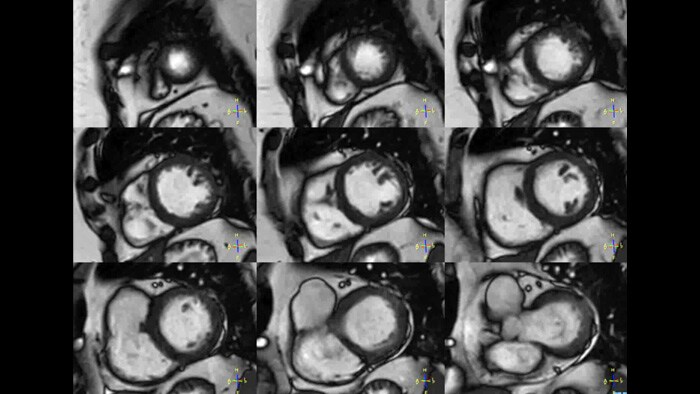

kt-SENSE

Clinical application kt-SENSE

Clinical Area

Cardiac

Co-Creation Facility ETH Zürich, Switserland